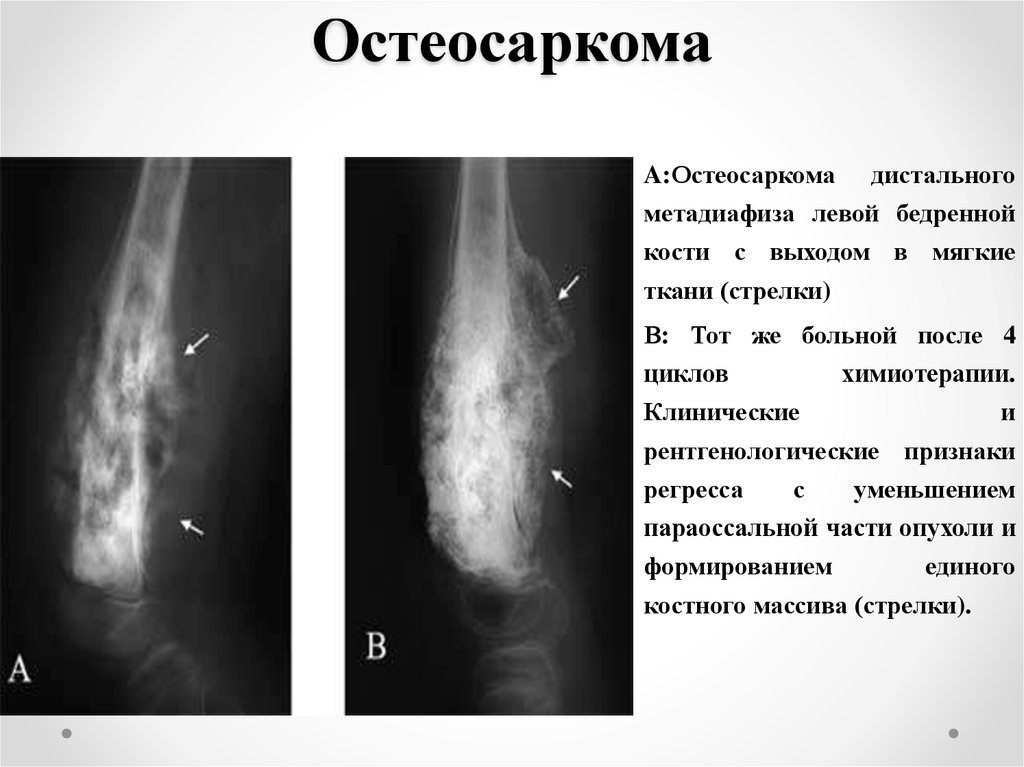

Рентгенологическая картина остеогенной саркомы кости - 98 фото